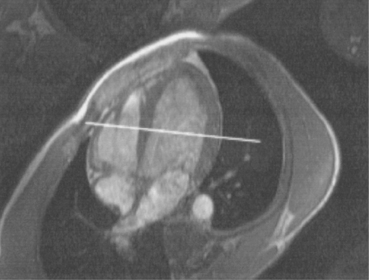

The right atrium forms the right border of the heart and receives deoxygenated blood from the body via the superior and inferior venae cavae and from the coronary sinus and cardiac veins that drain the myocardium. A small muscular embryonic appendage, the right auricle, projects upward and toward the left from the right atrium, covering the root of the aorta (Figure 6.40). The right ventricle lies on the diaphragm and comprises the largest portion of the anterior surface of the heart. It receives deoxygenated blood from the right atrium and forces it into the pulmonary trunk for conveyance to the lungs. Projecting off the inferior surface of the ventricular walls are conical-shaped projections of cardiac muscle called papillary muscles that anchor the cusps of the tricuspid valve to the right ventricle (Figure 6.39). The left atrium lies posterior to the right atrium and is the most posterior surface of the heart. It also has an embryonic appendage, the left auricle, that projects to the left of the pulmonary trunk over the superior surface of the heart. The left atrium receives oxygenated blood directly from the lungs via the four pulmonary veins (two on each side). The left ventricle forms the apex, left border, and most of the inferior surface of the heart. It receives oxygenated blood from the left atrium and pumps it into the aorta for distribution throughout the systemic circuit. The myocardium of the left ventricle is normally three times thicker than that of the right ventricle, reflecting the force necessary to pump blood to the distant sites of the systemic circulation (Figures 6.41 through 6.52). Two papillary muscles project from the ventricular walls to anchor the bicuspid valve to the ventricle (Figures 6.39 and 6.47).

Figure 6.43 Axial, T1-weighted MR scan of left atrium.

Key: RV, Right ventricle; LV, left ventricle; LA, left atrium; RA, right atrium.

The two atrioventricular valves are found at the entrances to both ventricles and function to prevent backflow of blood between the atria and ventricles during ventricular contraction. These valves have leaflets that are attached to the papillary muscles by thin cords of fibrous tissue called chordae tendineae. The right atrioventricular valve, with three leaflets, is called the tricuspid valve, and the left atrioventricular valve, with two leaflets, is called the bicuspid (mitral) valve (Figures 6.39, 6.43, 6.44, 6.47, and 6.48).